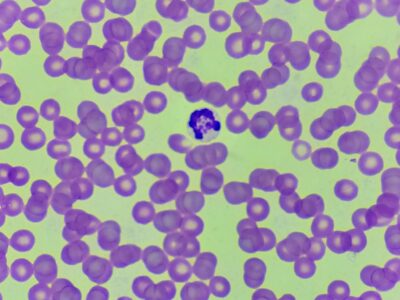

anaplasma inclusions

anaplasma inclusions -

anaplasma inclusions

anaplasma inclusions -